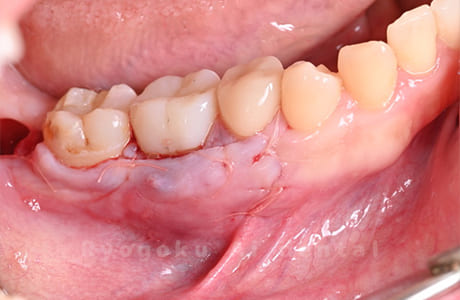

Case05

-

術後2ヶ月

- 原因

- 右下6番近心根パーフォーレーション

- 治療内容

- 外科的パーフォレーションリカバリー治療

- 治療費用

- ¥66,000

右下の奥から2番目の歯に穴が空いており、腫れが引かず、他院で抜歯と診断された患者様です。被せ物を外さずに、穴が空いている部分に外科的にアクセスし、その部分を修復手術を行いました。治療後も再発せず、経過良好です。

<リスク・副作用>

手術後は痛み、腫れ、痺れ、青あざなどの副作用が生じます。痛みは痛み止めを処方しますが、腫れ、青あざは1週間程度生じる場合があります。また、部位によっては神経の走行が複雑で、痺れが残り、長期的にお薬を処方する場合があります。